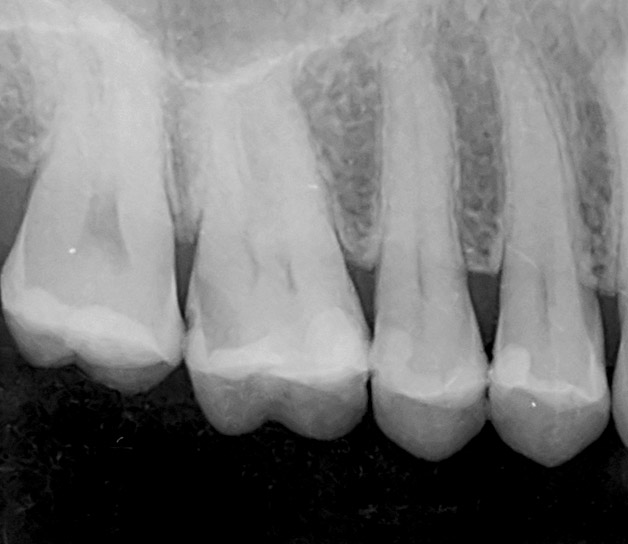

Radiografías periapicales y aletas de mordida

Mínima radiación para el estudio de dientes y hueso adyacente

Se trata de radiografías intraorales que con una mínima radiación aportan un gran detalle de los dientes y hueso adyacentes.

Normalmente se realizan para diagnosticar con precisión caries, enfermedad periodontal o fracturas de dientes, entre otras patologías.

Gracias a la tecnología digital, estas imágenes se procesan en cuestión de segundos y aportan mucha más nitidez y precisión que las convencionales.